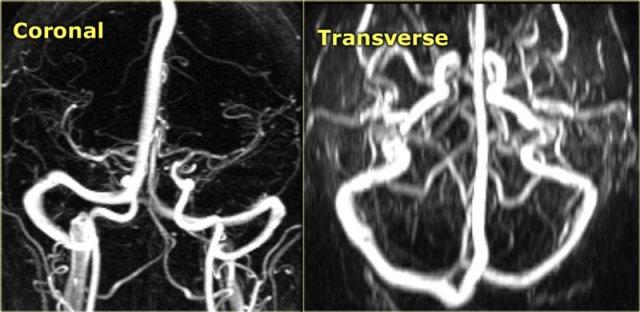

Chụp tĩnh mạch MR (MR-venography)

Các kỹ thuật MRI được sử dụng để chẩn đoán huyết khối tĩnh mạch não bao gồm:

Chụp mạch thời gian bay (Time-of-flight – TOF), chụp mạch tương phản pha (Phase-contrast angiography – PCA) và chụp tĩnh mạch MR có tiêm thuốc tương phản từ:

-

Chụp mạch thời gian bay (TOF) dựa trên hiện tượng tăng tín hiệu liên quan đến dòng chảy của các spin đi vào lớp cắt.

Do chưa bị bão hòa, các spin này tạo ra tín hiệu mạnh hơn so với các spin xung quanh đã bị bão hòa. - Chụp mạch tương phản pha (PCA) sử dụng nguyên lý rằng các spin trong máu di chuyển cùng chiều với gradient từ trường sẽ tạo ra độ lệch pha tỷ lệ thuận với vận tốc của các spin.

Thông tin này có thể được dùng để xác định vận tốc của các spin. Hình ảnh này có thể được trừ đi từ hình ảnh thu được mà không có gradient mã hóa vận tốc để tạo ra hình ảnh mạch máu. - Chụp tĩnh mạch MR có tiêm thuốc tương phản từ sử dụng hiệu ứng rút ngắn thời gian T1 của Gadolinium.

Kỹ thuật này tương tự như chụp tĩnh mạch cản quang CT.

Khi sử dụng hình ảnh tái tạo MIP, luôn luôn phải xem xét các hình ảnh gốc (source images).

Bên trái là hình ảnh MIP theo mặt phẳng đứng dọc và chếch của một ca chụp tĩnh mạch MR có tiêm thuốc tương phản từ bình thường.

Lưu ý tĩnh mạch Trolard nổi bật (mũi tên đỏ) và tĩnh mạch Labbe (mũi tên xanh lam).

Mỗi kỹ thuật MRI đều có những bẫy chẩn đoán riêng mà chúng ta sẽ thảo luận sau.

Chụp tĩnh mạch MR có tiêm thuốc tương phản từ có nhược điểm là cần tiêm thuốc, nhưng có ít bẫy chẩn đoán hơn.